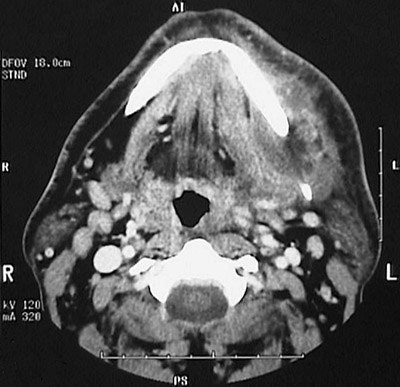

| In the axial CT scan view seen here, an odontogenic abscess has extended into soft tissues below the mandible with overlying soft tissue swelling. With modern dental care, this is easily preventable and treatable, but in ancient times it was a cause of death. |